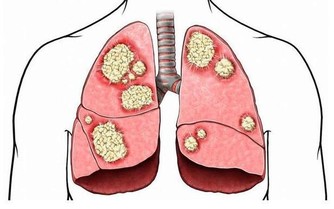

肝位於上腹部,肝癌初期並無徵兆,一般人難以察覺,

甚至當腫瘤增大至十公分以上時,有的人還是缺乏典型症狀。

當肝臟腫瘤逐步增大,有可能會壓迫附近的橫膈膜,亦可壓著肺部以下的肌肉神經。